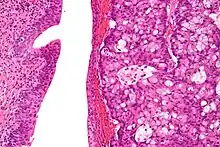

Micrograph of urachal carcinoma (right of image) and non-malignant urothelium (left of image). H&E stain.

Urachal cancer usually is an adenocarcinoma (about 90%) mostly with mucinous/colloidal histology. Other rare types include urothelial carcinoma, squamous cell carcinoma, neuroendocrine carcinoma and sarcoma.[2][4][7][8]